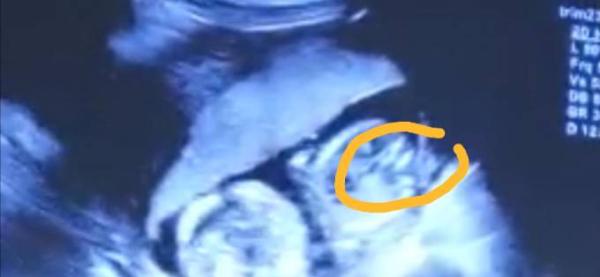

Huhu liebe Mamas also ich hab mir mein Video noch und nöcher angeschaut und ich seh da absolut keinen Buben mir ist es letzen Endes egal qaas es wird Hauptsache gesund aber ich würde es schon gerne wissen bin so neugierig was sagt ihr dazu

Bild zu Junge oder Mädchen?🤔 - Forum für Januar - Mamis